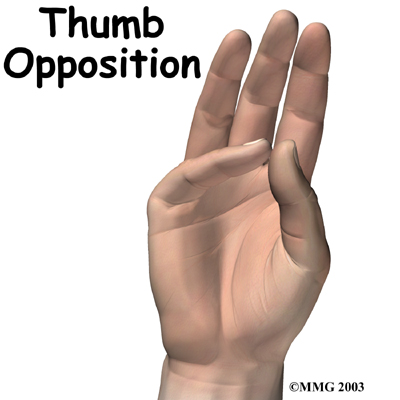

The carpometacarpal joint of the thumb (CMC joint) is where the metacarpal bone of the thumb attaches to the trapezium bone of the wrist. This joint is sometimes referred to as the basal joint of the thumb as it is the joint closest to the bottom of the hand. The CMC is the joint that allows you to move your thumb into your palm, a motion called opposition.